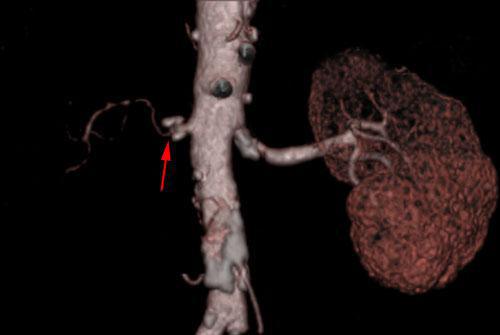

Estenosis por displasia fibromuscular de arterias renales